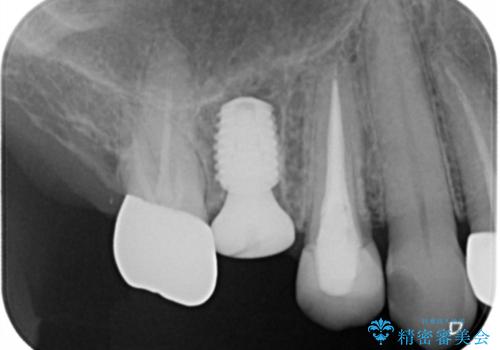

インプラント治療を希望されたので治療の期間・回数の少ない抜歯即時埋入インプラントでの治療を計画しました。

抜歯と同時にインプラントを埋入することで治療の期間・回数を減らし、患者様への負担を大幅に軽減することができます。

今回の患者様においては、術後に痛みは発生せず良好な経過を得ることが出来ました。